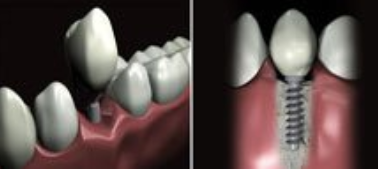

FICHE CLINIQUE Prothèse fixée conventionnelle : Couronnes et bridges